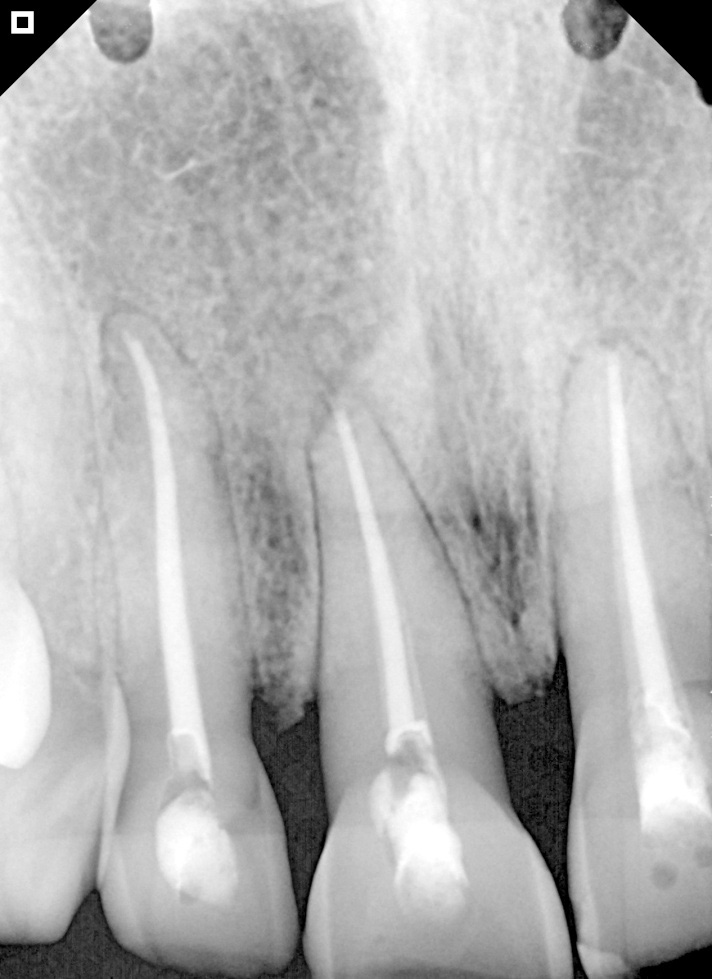

Radiography of gutta-percha cones.

Final radiography (immediate postoperative).